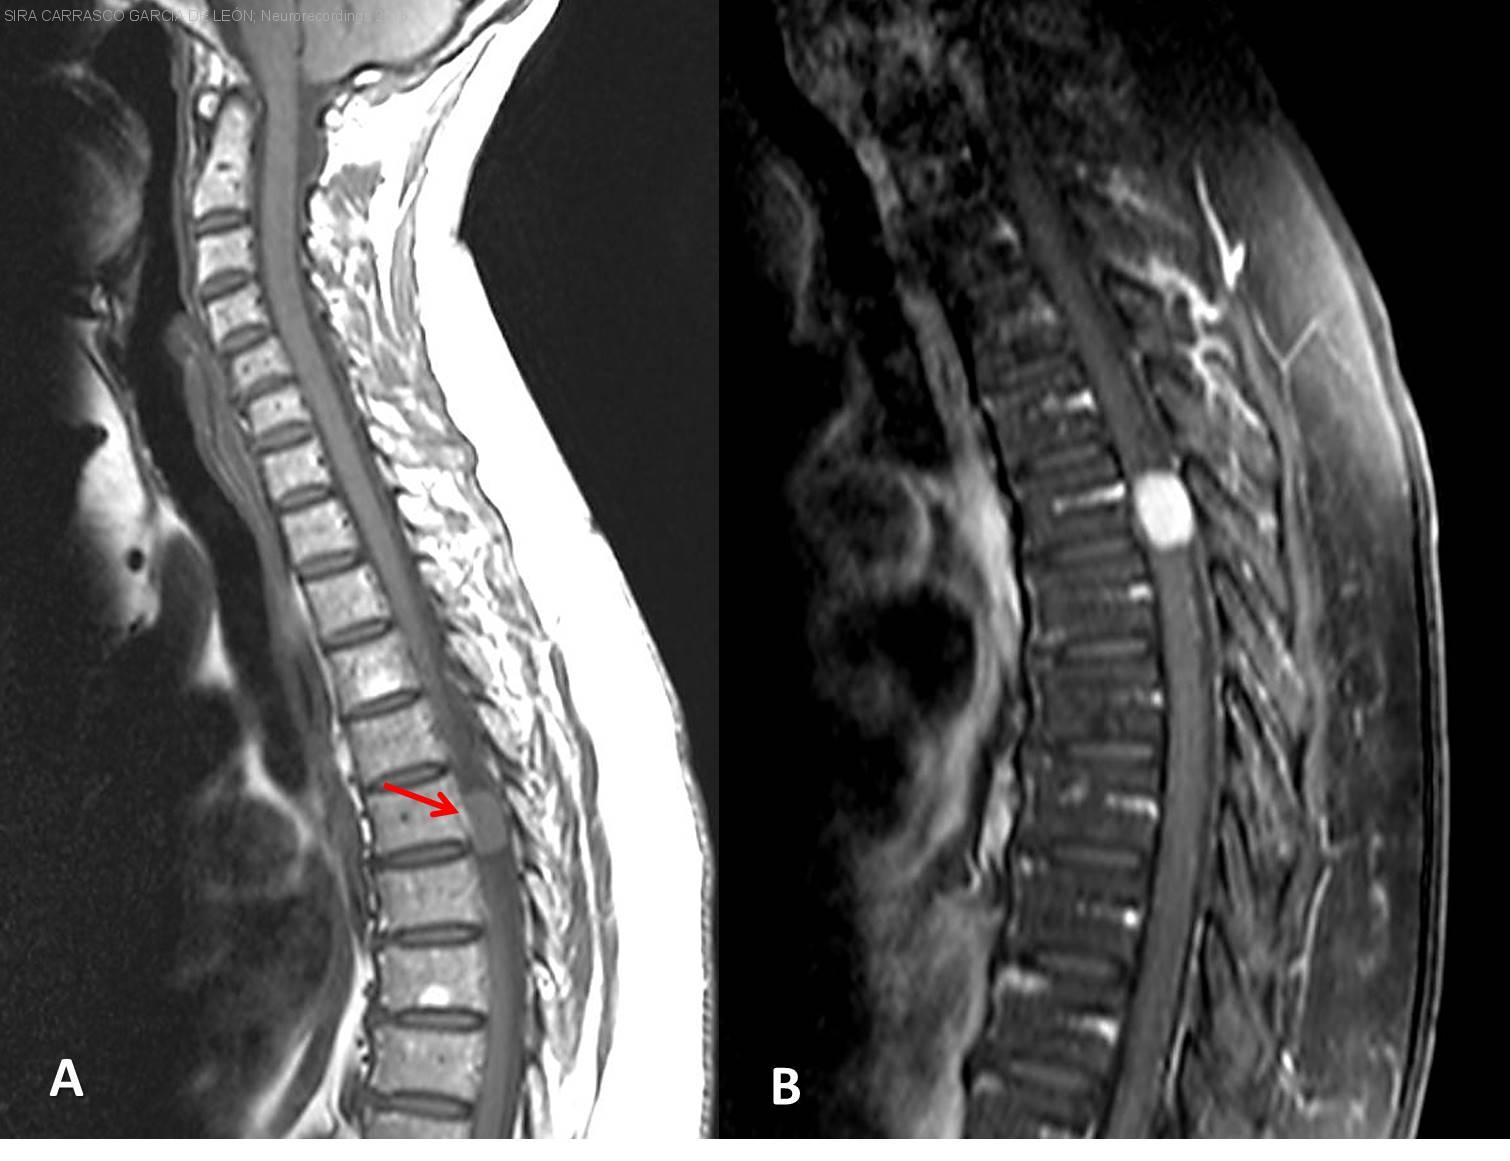

Mujer | 68 años

Diagnóstico final: Meningioma espinal dorsal grado I

Mujer de 68 años, refería sensación de quemazón, disestesias e hiperestesia provocada por estímulos mínimos en el costado derecho, desde hacía 4 meses. Aunque en ningún momento presentó lesiones vesiculosas, fue diagnosticada y tratada como...